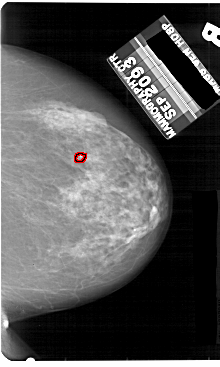

A_1859_1.RIGHT_MLO

RIGHT_CC LINES 5491 PIXELS_PER_LINE 3286 BITS_PER_PIXEL 12 RESOLUTION 43.5 OVERLAY

FILE: A_1859_1.RIGHT_CC.OVERLAY

TOTAL_ABNORMALITIES 1

ABNORMALITY 1

LESION_TYPE CALCIFICATION TYPE PLEOMORPHIC DISTRIBUTION CLUSTERED

ASSESSMENT 4

SUBTLETY 4

PATHOLOGY BENIGN

TOTAL_OUTLINES 1

BOUNDARY